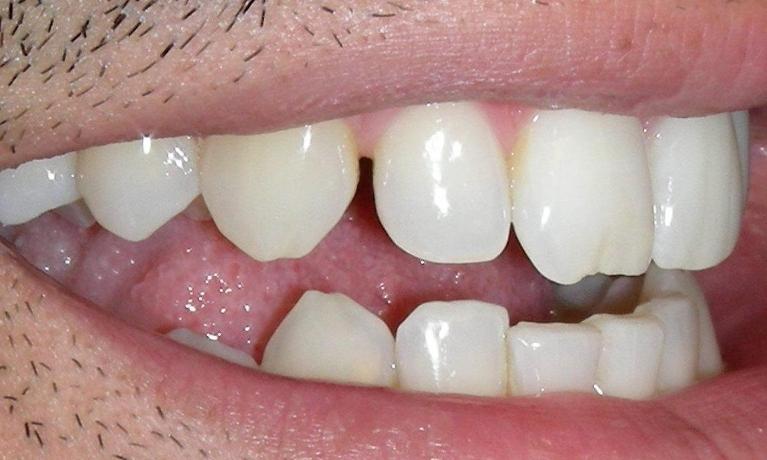

Before

After

Porcelain Veneers

These porcelain veneers replaced the ones the patient had received several years earlier.